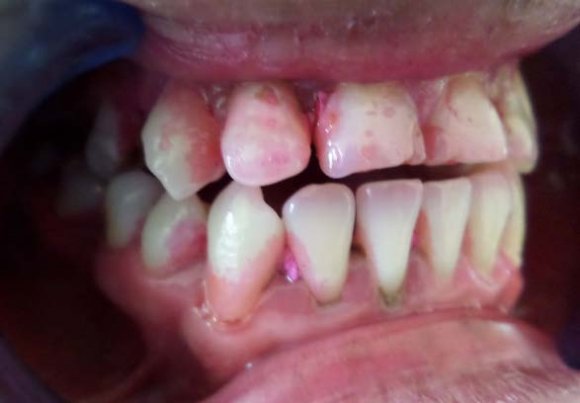

After post obtuaration restoration, crown preparation was done and PFM crown placed. During the first visit after isolation was done using rubber dam (Hygiene Dental Dam, Coltene Whaledent, Germany). A cavity was prepared and working length was determined using apex locator (Root ZX II, Morita Tokyo, Japan) (figure 6). Biomechanical preparation was done using hand stainless steel file till 70K wrt 21 and till 50K wrt 22 along with the copious irrigation with 5.25% sodium hypochlorite. An intracanal medicament dressing of calcium hydroxide was given and the tooth was sealed with provisional material.

After 7 days the intracanal dressing was changed for another obtaining by mixing calcium hydroxide powder and tooth was sealed. On third visit the intracanal dressing was removed and the canal was irrigated with 17% EDTA and master cone radiograph was taken (figure 7). 21 was obturated with the lateral cold compaction technique and the portion of the canal below the resorptive defect was obturated with gutta percha (Dentsply, Maillefier Germany) and A H plus sealer (Dentsply, Maillefier Germany) using sectional condensation technique and the remaining canal was obturated with thermoplastized gutta percha technique. Then final restoration with composite was done followed with prosthesis (figure 8). In 21 root canal treatment was started with straight line access, working length was determined using radiograph(figure 10) and bleeding point was check using paper point. Biomechanical was done till 80K stainless steel file under copious irrigation with saline. Calcium hydroxide intracanal medicament was place for 2 week and cavity was sealed with temporary material. Following copious irrigation with 5% sodium hypochlorite, calcium hydroxide powder mix was renewed after a week.